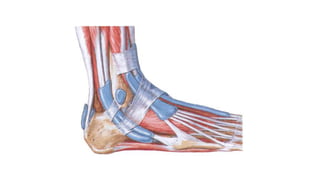

FRACTURA TIBIOPERONEA

REGION PIE